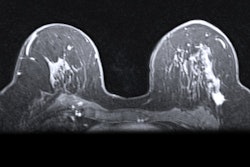

Radiologists with at least 11 years of interventional experience performed 42 mammographic and 19 sonographic hooked wire localizations in the initial trial. The wires were placed between 16 and 25 hours before surgery, with a median time of about 20 hours.

Mammography performed on the day of surgery revealed that the wires migrated 2 mm on average. However, none of the wires needed adjustment before surgery.

Based on the success of the first trial, the institution approved the use of wire localization on the day prior to surgery for all patients. During a five-month period in 2019, the same radiologists performed 52 mammographic and 7 sonographic looped wire localizations.

Similar to the first trial, an average of about 19 hours passed between wire placement and breast surgery. The wires moved about 1 mm on average, and once again, no wires needed adjustment.